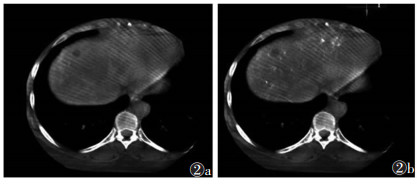

2 结果100例中, 56例可重建出CBCT动脉期三维血管图像(图 1b), 并依据血管走行超选择插管到位顺利并成功栓塞。栓塞后CBCT平扫可评价栓塞效果(图 1c)。3例存在动脉期显示不明显而静脉期显示的病灶(图 2), 余46例动脉期与静脉期均可分辨病灶(图 3)。

| 图 2 女,51岁,肝癌射频消融术后 图 2a CBCT动脉期显示不清晰的病灶 图 2b静脉期病灶清晰强化(白箭) |